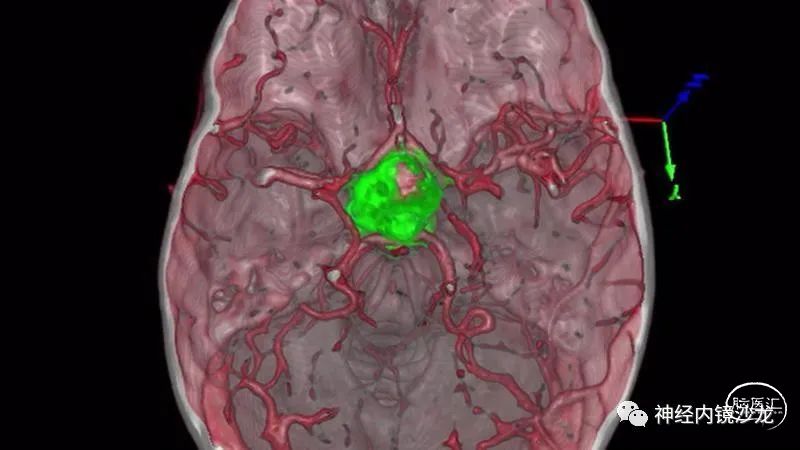

采用虚拟现实模拟和3D打印技术来评估鼻窦气化不良和鼻腔的整体大小是否影响手术操作。我们的实验室结果表明双侧鼻腔入路可行。

手术暴露充分术野,从蝶骨平台到斜坡,从眼眶到眼眶。切除大块钙化部分肿瘤后,我们找到肿瘤包膜和下丘脑、视觉通路之间的清晰的分离平面。切除结束时,发生了后交通动脉从大脑后动脉撕脱导致的动脉出血。采用单轴持夹器放置一个成角的动脉瘤夹,以夹闭损伤部位并保证供血动脉不狭窄。术后即刻和晚期磁共振成像和CTA检查显示肿瘤全切、无卒中、无假性动脉瘤形成。